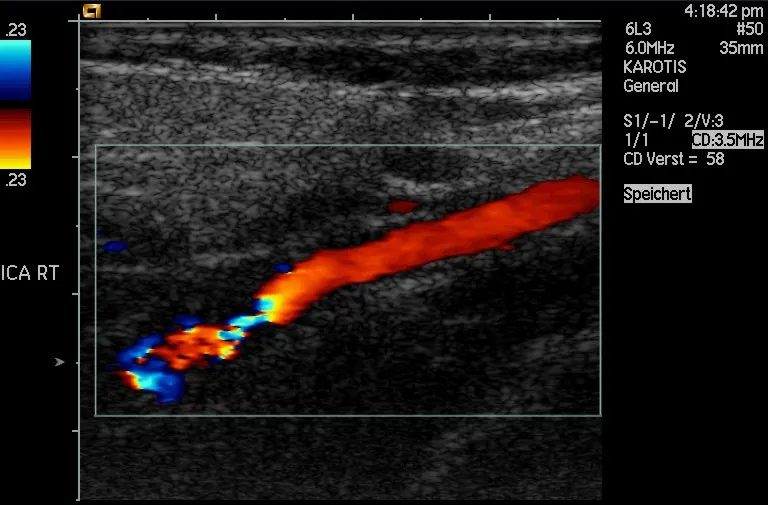

Another major use of ultrasound in medical diagnostics is to detect motion and determine velocity through the Doppler shift of an echo, known as Doppler-shifted ultrasound. This technique is used to monitor fetal heartbeat, measure blood velocity, and detect occlusions in blood vessels, for example. (See Figure 17.45.) The magnitude of the Doppler shift in an echo is directly proportional to the velocity of whatever reflects the sound. Because an echo is involved, there is actually a double shift. The first occurs because the reflector (say a fetal heart) is a moving observer and receives a Doppler-shifted frequency. The reflector then acts as a moving source, producing a second Doppler shift.

Doppler-shifted ultrasonic image of a partially occluded artery.

Figure 17.45 This Doppler-shifted ultrasonic image of a partially occluded artery uses color to indicate velocity. The highest velocities are in red, while the lowest are blue. The blood must move faster through the constriction to carry the same flow. (credit: Arning C, Grzyska U, Wikimedia Commons)

A clever technique is used to measure the Doppler shift in an echo. The frequency of the echoed sound is superimposed on the broadcast frequency, producing beats. The beat frequency is FB=f1f2FB=f1f2, and so it is directly proportional to the Doppler shift (f1f2f1f2) and hence, the reflector’s velocity. The advantage in this technique is that the Doppler shift is small (because the reflector’s velocity is small), so that great accuracy would be needed to measure the shift directly. But measuring the beat frequency is easy, and it is not affected if the broadcast frequency varies somewhat. Furthermore, the beat frequency is in the audible range and can be amplified for audio feedback to the medical observer.